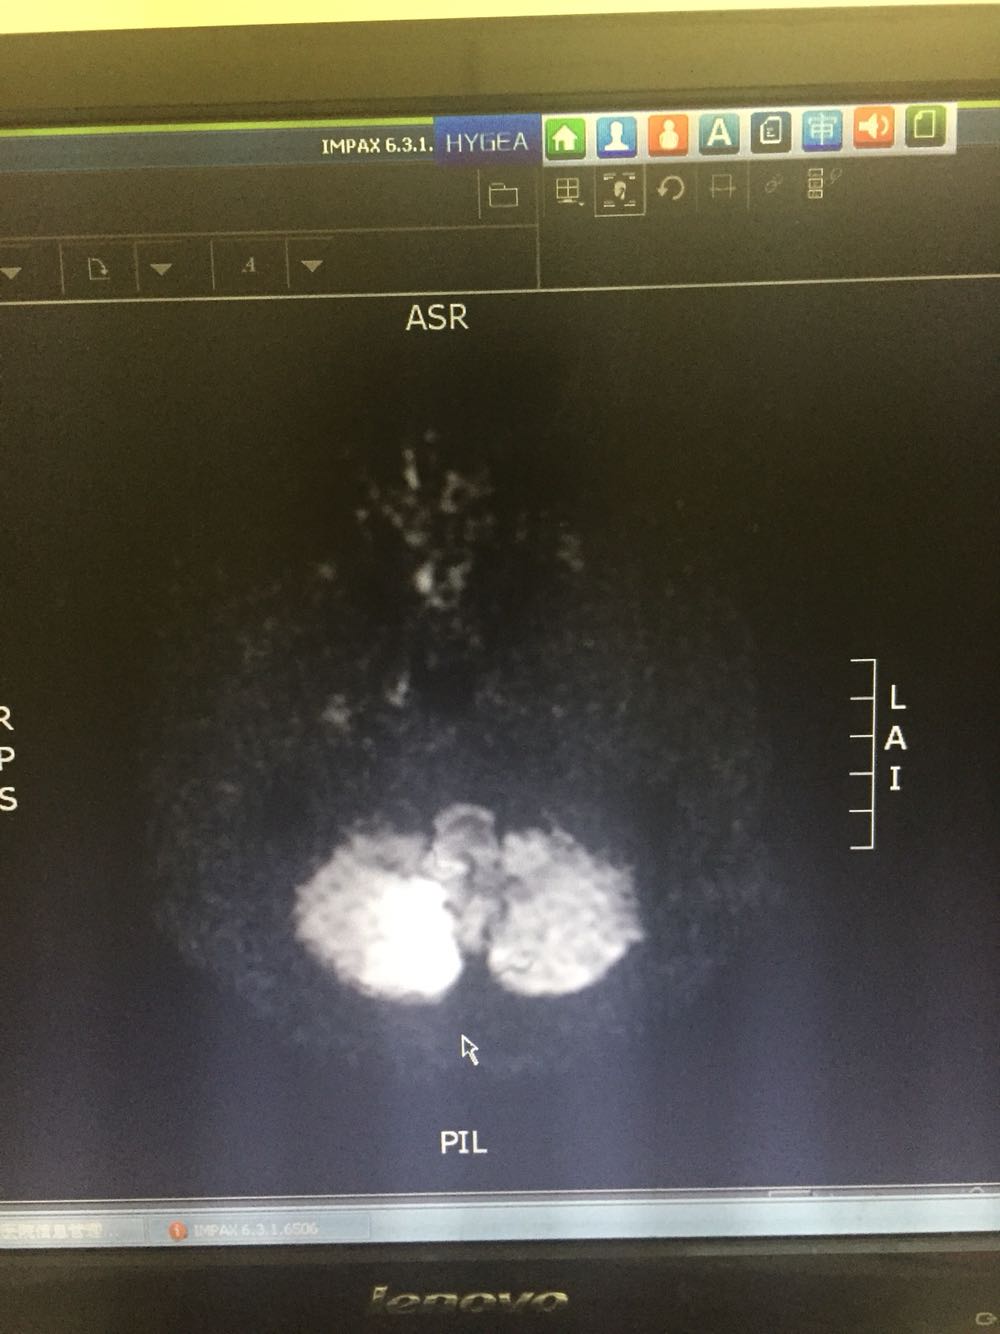

76岁女患,因眩晕三小时入院 既往高血压3年,冠心病史 该患者于入院前三小时无明显诱因出现眩晕,伴有恶心、头痛,无呕吐,病程中无肢体活动障碍,无言语不清,无意识障碍及尿便失禁,不伴有耳鸣及听力减退,为求进一步诊治而来我院。 血、尿化验未见明显异常

诊断:脑梗死、高血压 治疗:改善循环、抗血小板聚集、营养神经、调控血压对症治疗

主要注意与基地动脉尖综合症相鉴别。该患者右侧P2及左侧P3段局限性狭窄